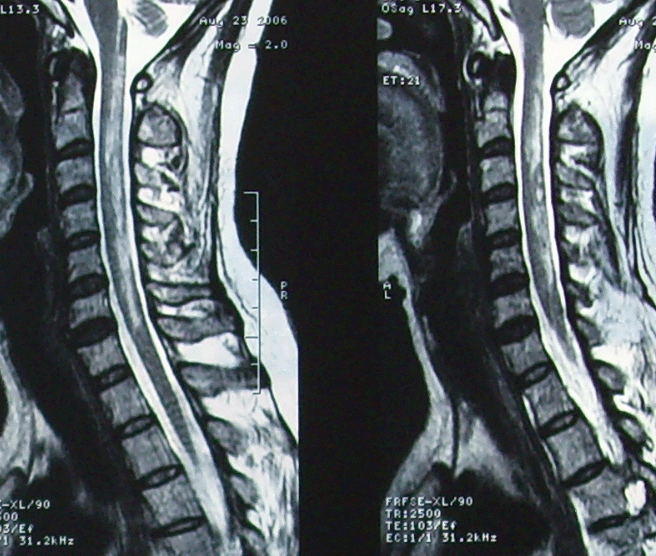

脊髓病的核磁成像特点

1,急性脊髓炎:多在t3-5段最常见,mri表现病变部位脊髓增粗,病变节段髓